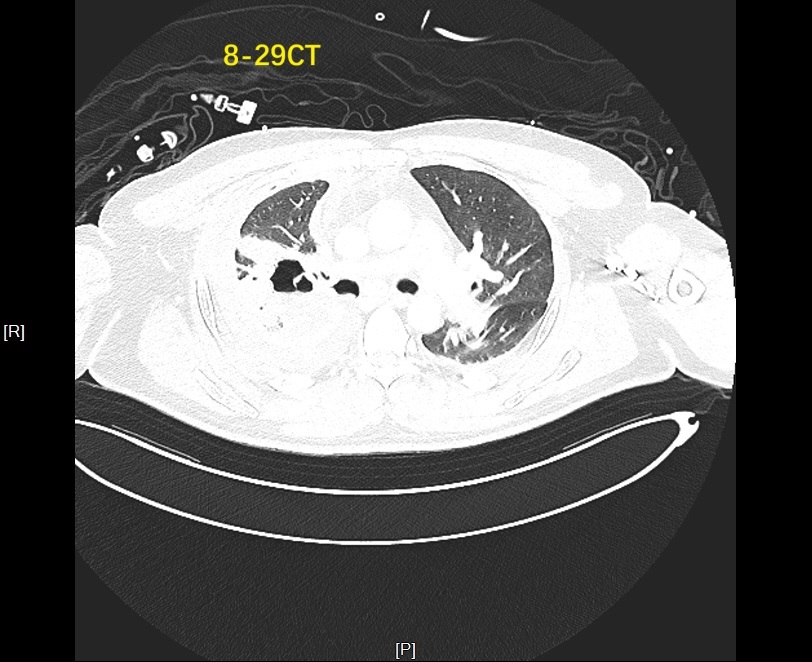

图为患者支气管胸膜瘘发生严重感染

支气管胸膜瘘被称为胸外科治疗中的“硬骨头”,其瘘口周围组织常伴随炎症、血供不良等问题,且易出现复杂的气流异常,给治疗带来极大挑战。中大医院呼吸与危重症医学科副主任丁明副主任医师带领的介入团队接诊后,首先通过术前CT初步锁定右上叶后段为疑似瘘口位置,但要确保封堵精准,还需更精密的检测。